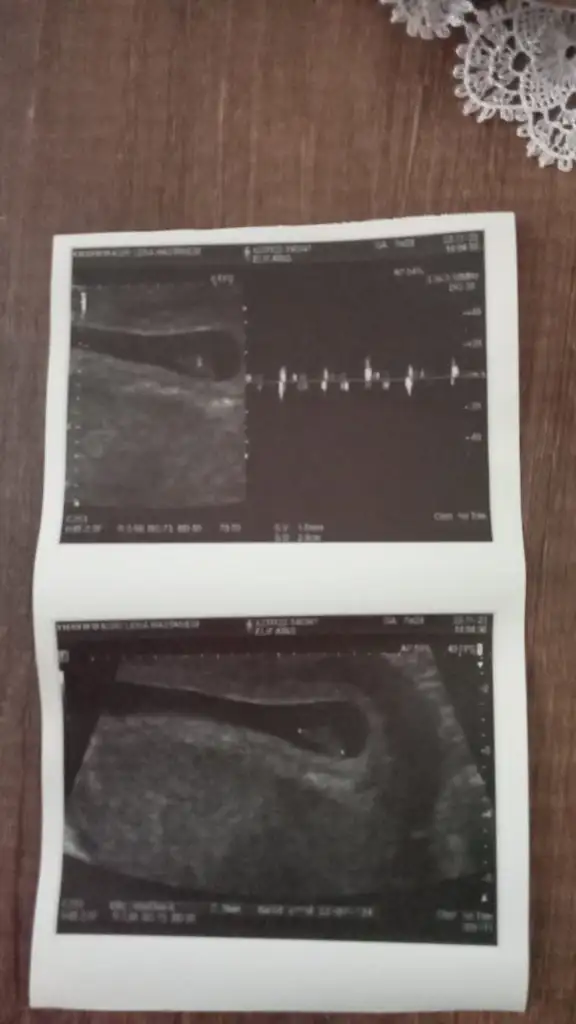

7.haftada solda 8. Haftada sağda hangisi doğru şimdiRamzi teorisine göre ( bilimsel bir araştırma sonucuymuş ve %85 doğruluğu varmış). İlk 6-8 haftalık ultrason görüntüsüne göre bebeğin kesenin içersinde soldan ya da sağdan girişine göre cinsiyet tahmini yapılıyor. Bilimsel olunca tecrübeli annelerimiz yada anne adaylarımızdan yardım istiyoruz. Doğruluğu var mı öğrenmek adına :) Bizleri aydınlatırsanız çok seviniriz. bu teorieye göre;